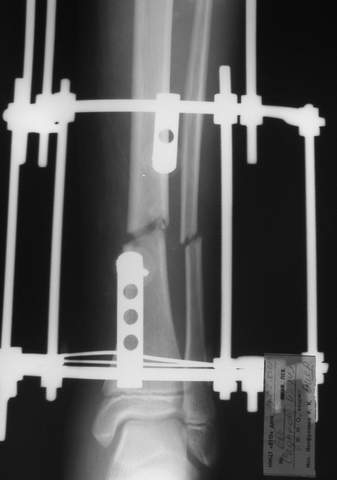

МТ мы используем, конечно, не только на голени. В прилагаемом примере у парня при поступлении была наружная ротация 40 гр. и "полумертвый" коленный сустав. Можно был бы, конечно, до конца использовать полную компоновку. Но для того он и есть метод выбора.